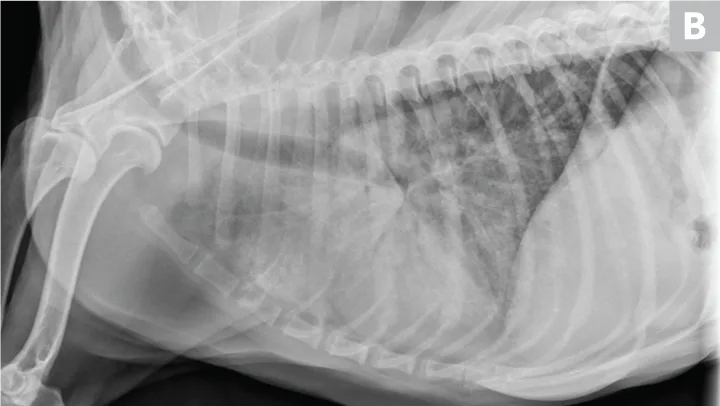

CDV should be suspected in poorly vaccinated dogs with multiorgan involvement. Dogs with CDV may have exhibited only respiratory signs before developing characteristic nonrespiratory signs.12 Radiographs may reveal a diffuse interstitial pattern (Figure 2). Diagnosis is supported by compatible clinical signs and complementary diagnostic testing (ie, real-time reverse transcription polymerase chain reaction [RT-PCR], serology, CSF pleocytosis). Conjunctival scraping and tissue-based immunohistochemistry may confirm diagnosis.

FIGURE 2

CDV pneumonia with a diffuse interstitial pattern confirmed by multisystemic signs, urine RT-PCR, and necropsy